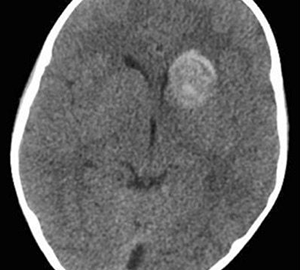

Paciente de 4 años. TEC, Vómitos.